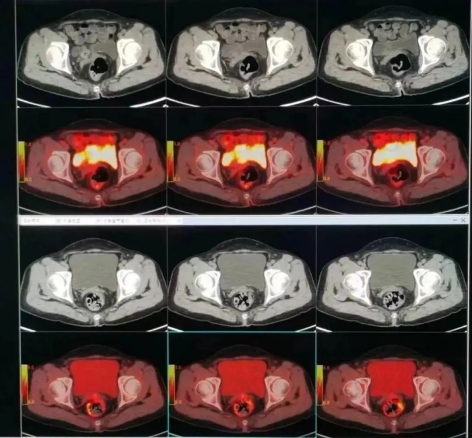

▲ 子宫内膜癌术后复发病例扫描图

2.更强诊断力,检查更暖心。传统影像检查发现器官肿瘤时,尤其是在病变早期,很难判断是良性还是恶性。但PET/CT检查可以根据病灶高代谢的特点做出诊断。